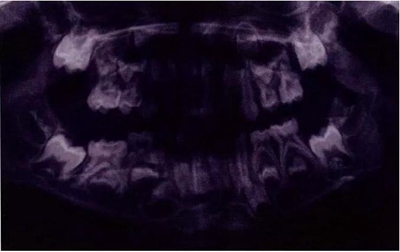

圖8展示了一張5歲孩子右下第二乳磨牙嚴(yán)重下沉的口內(nèi)像。臨床檢查可見右下第一乳磨牙遠(yuǎn)中傾斜,朝向下沉乳牙。X線片檢查顯示所有恒牙胚都存在(圖9)。無論是臨床還是影像學(xué),都可檢查到有齲齒的存在。鑒于這顆下沉乳牙在年齡較小時(shí)就已經(jīng)非常嚴(yán)重,同時(shí)還患有齲病,因此決定予以拔除。后期在放置間隙保持器的同時(shí)還應(yīng)持續(xù)觀察監(jiān)測(cè)右下第一恒磨牙和第二前磨牙的萌出情況。

圖9:一名五歲患兒右側(cè)下頜第二乳磨牙嚴(yán)重下沉的曲面體層片